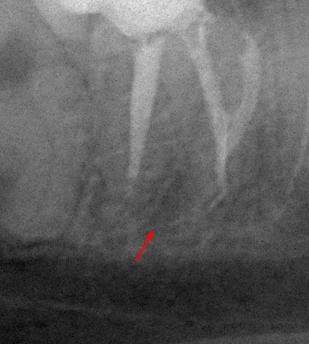

Пациентка 28 лет обратилась с жалобами на приступообразную ночную боль в области нижней челюсти справа.

На жевательной поверхности 47 зуба глубокая кариозная полость в пределах околопульпарного дентина, пульповая камера не вскрыта, зондирование болезненное, перкуссия безболезненная, холодовой тест резко болезненный, после удаления раздражителя болевая реакция продолжается в течении 20-ти секунд.

Диагноз: необратимый пульпит 47-го зуба.

На рентгенологических снимках представлена картина до лечения, диагностический снимок и конечный результат.